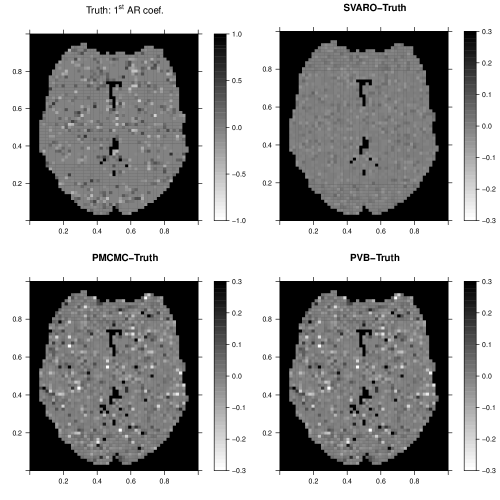

Next we compare SVARO with PVB and PMCMC in estimating the st AR coefficient. As shown in Figure 3, SVARO shows little error compared with the truth, indicating that our model has captured the autoregressive parameter quite well. In contrast, PMCMC and PVB exhibit more bias, indicating a lack of fit for the temporal noise. Note that we are only displaying the SVARO estimates for the st AR coefficient for simplicity and direct comparison, the other AR coefficients are similarly well-estimated.

We plot the posterior probability maps (PPM) in Figure 5. This figure depicts the locations of the true activations and the posterior probability maps from SVARO. In addition, differences in the probability maps comparing SVARO with PMCMC and PVB are also depicted. Again, SVARO appears to perform the best in producing the highest posterior probabilities for regions that are truly activated. PMCMC is similar to SVARO but its probability on those activated regions are slightly lower than those from SVARO, especially on the boundary. PVB under performs compared with the other two approaches by providing greater posterior probability on null locations while providing smaller posterior probability on actived locations.